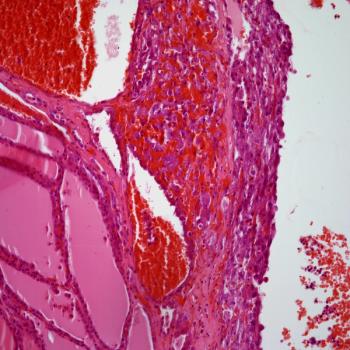

A 68-year-old woman presents with presents with a mass in the tail of the pancreas. What is your diagnosis?